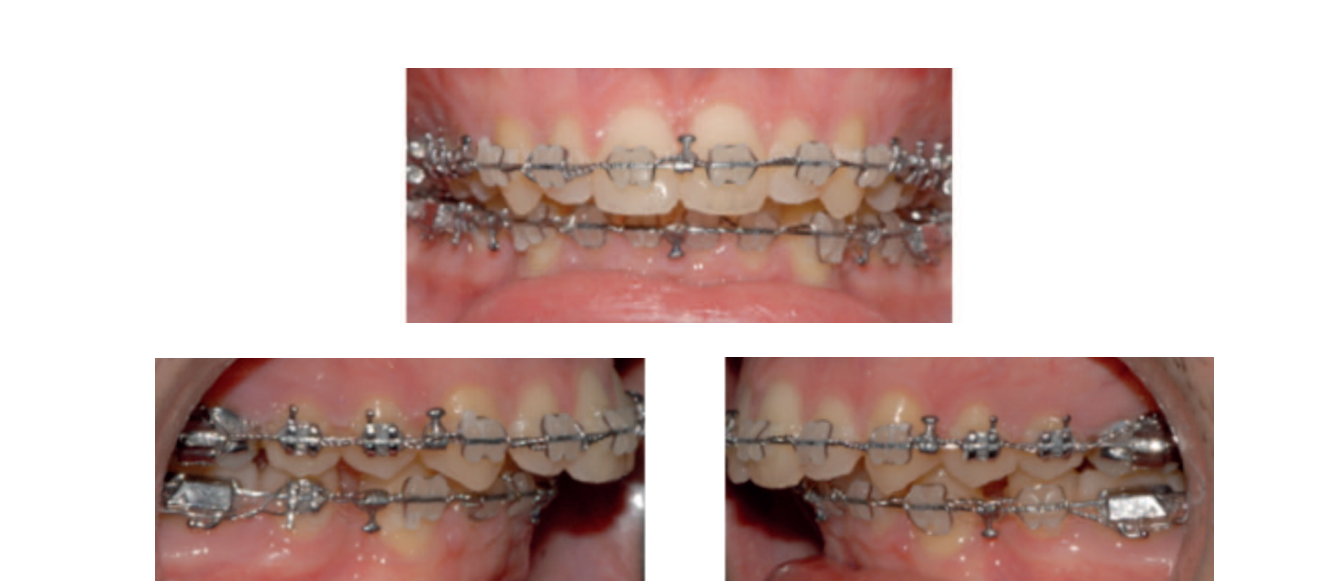

В дентальном анализе (рис. 4) наблюдается: легкое сжатие сзади из-за недостатка торсии в молярах и премолярах; класс II по молярам и клыкам с обеих сторон; отсутствие выступа из-за проинклинации нижних резцов; переднее скученность в обеих дугах и множественные ротации, а также сильная проинклинация нижних резцов.

После выравнивания нижней кривой Спи и коррекции наклона нижних резцов наша предоперационная ортодонтическая цель достигнута. Потеря задней опоры для завершения закрытия пространств после экстракции может быть отложена на послеоперационную фазу, используя RAP (феномен регионального ускорения).